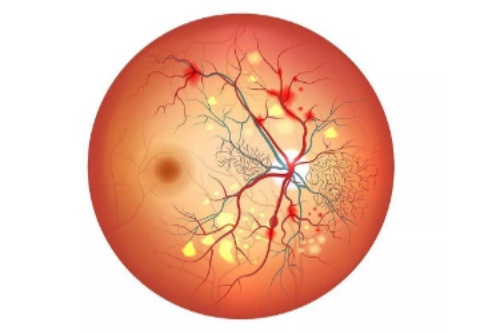

在探讨眼科疾病治疗时,眼底病的治疗备受关注,而武汉协和医院在这方面的表现值得深入了解。

很多人会问:武汉协和医院治疗眼底病好吗?下面从多个维度为大家分析。

在眼底病治疗方面,医生们能够运用可靠的技术和丰富的经验,为患者制定个性化的治疗方案。